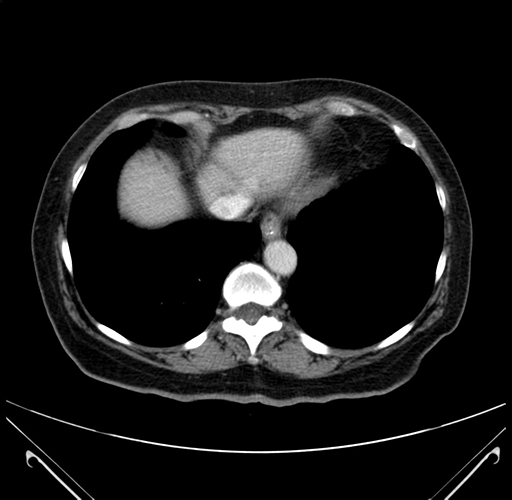

Pre-Chemo: Axial Venous

Axial Venous